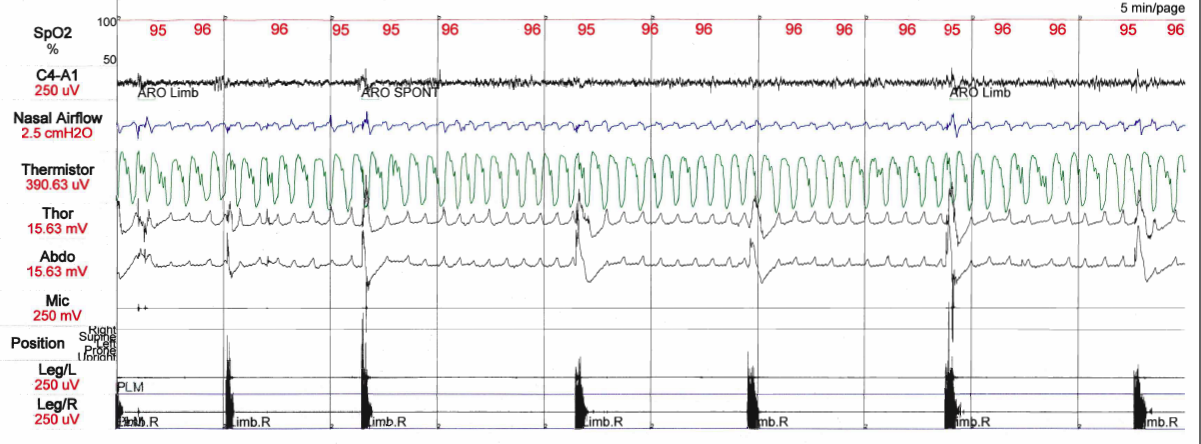

The diagnosis is based on a patient having disturbed sleep and by recording activity while the person is participating in a sleep study (polysomnography). During a sleep study, repetitive twitching of limbs can be recorded. Such patients often have trouble sleeping and may have leg twitching before falling asleep but most often this happens while they are asleep.

PLMD is diagnosed by noting physical symptoms and by performing a sleep study in which muscle contractions are recorded. RLS is diagnosed by noting physical symptoms.